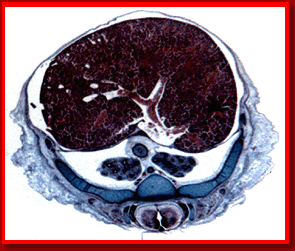

CORTE TRANSVERSAL DE UN FETO

Diafrágma

Aorta

Esófago

Vértebras

Costillas

Pulmones

Hígado

Médula Espinal